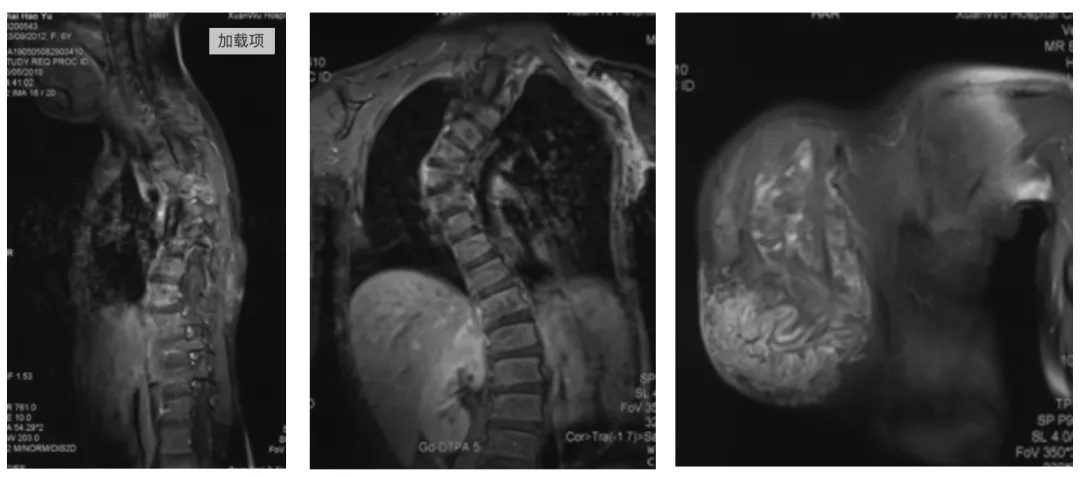

2. Thoracic spine MRI suggesting huge subcutaneous mass with scoliosis

Postoperative MRI + enhancement